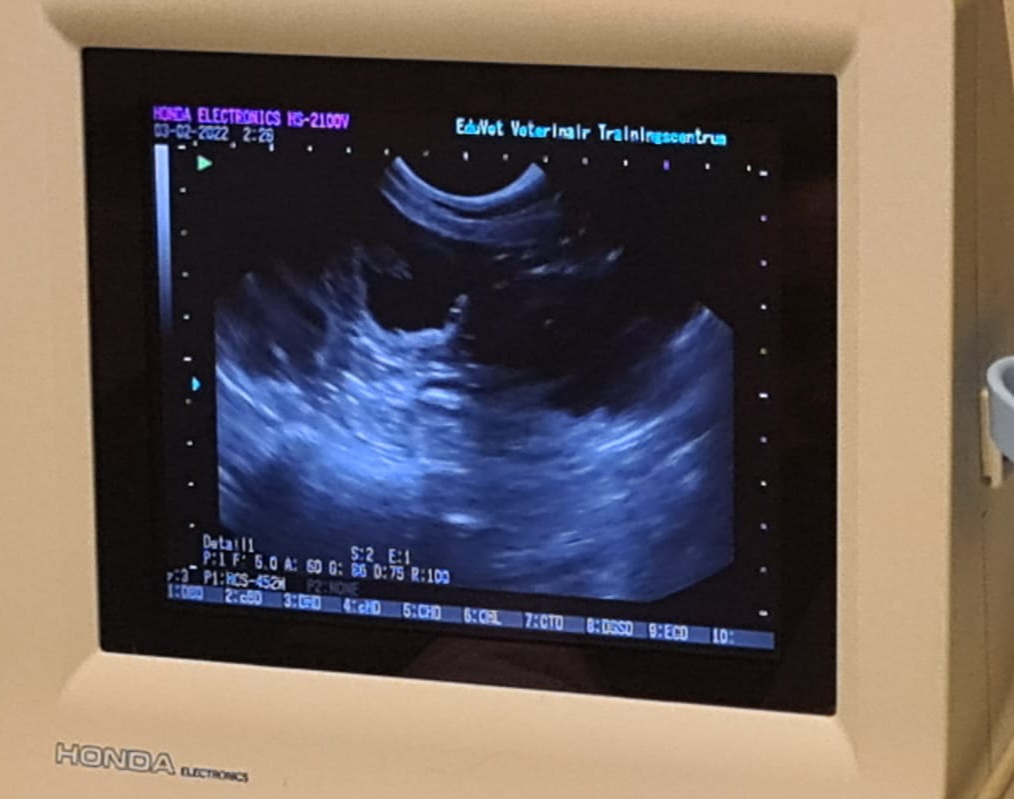

echo bevestiging zwangerschap

De pups worden verwacht rond 22 maart 2026.